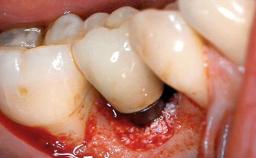

A 27-year-old male was referred to the periodontist for assessment and management of implant site 41. The implant had been placed nine years previously and restored with a screw-retained single crown. The patient was a cigarette smoker in good general health. He reported he had reduced his smoking habit from 25 cigarettes per day to 15 cigarettes per day in the previous six months. On examination, there was calculus and plaque present at the lower anterior teeth and at implant site 41. Localized attachment loss was observed at teeth 32 and 42, with 2–3 mm of gingival recession. At implant site 41, there were 8–9 mm probing depths with suppuration and bleeding on probing.